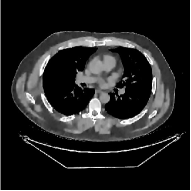

This section compares the reconstruction quality and runtime among the proposed MBIR method, PWLS-ST-, and other three MBIR methods, PWLS-EP, PWLS-DL, and PWLS-ST-. Table I shows that, for both 2D and 3D sparse-view CT reconstructions of the XCAT phantom, the proposed PWLS-ST- model outperforms PWLS-EP and PWLS-ST- in terms of RMSE. In addition, PWLS-ST- using a square transform (of size ) achieves lower RMSE than PWLS-DL using an overcomplete dictionary (of size ) for 2D sparse-view reconstructions. Fig. 3(a) and Fig. 4 show the reconstructed images for 2D and 3D phantom experiments, with different reconstruction models and different number of views. (See the corresponding error maps in the supplement.) The proposed PWLS-ST- consistently gives more accurate image reconstructions compared to other MBIR methods. Specifically, PWLS-ST- has smaller errors in the heart region (see zoom-ins in Fig. 3(a)) of 2D reconstructions than PWLS-DL and PWLS-ST-. In addition, compared to PWLS-ST-, PWLS-DL and PWLS-ST- have some ringing artifacts around the edges with high transition, e.g., edges between air and soft tissues. (See a comparison of profiles of PWLS-ST- and PWLS-ST- in the supplement.) In particular, PWLS-ST- and PWLS-DL give more visible ringing artifacts for 2D reconstruction from fewer views, and PWLS-ST- has these ringing artifacts for 3D reconstructions regardless of the number of views (see zoom-ins in Fig. 4). Table II reports runtimes of different MBIR methods in reconstructing the -views XCAT phantom scan. (FBPConvNet is a non-MBIR method and its runtime for processing a image is approximately one second with a TITAN Xp GPU.) While providing better reconstruction quality, the proposed Algorithm 1 of PWLS-ST- has shorter runtime compared to the algorithms of PWLS-DL and PWLS-ST- in Section III-A. Similar to the PWLS-EP algorithm, the reconstruction time of the PWLS-DL, PWLS-ST-, and PWLS-ST- algorithms can be further reduced by using ordered subsets [51].

Fig. 3(b) shows that when tested on the clinical scan data, the proposed PWLS-ST- method improves reconstruction quality in terms of noise and artifacts removal (e.g., see zoom-ins for soft-issue regions), and edge preservation (e.g., see zoom-ins for bone regions), compared to PWLS-EP and PWLS-ST-. Compared to PWLS-DL, PWLS-ST- achieves comparable image quality, but requires less computational complexity.

The benefit of the proposed PWLS-ST- over PWLS-ST- can be explained when there exist some outliers for some : in (12) gives equal emphasis to all sparse codes – from small to large coefficients that generally correspond to edges in low- and high-contrast regions, respectively – in estimating ; however, PWLS-ST- adjusts to mainly minimize the outliers, i.e., it may not pay enough attention to reconstruct regions with small coefficients. The histogram results in Fig. 1 reveal model mismatch of PWLS-ST- over the iterations. Fig. 3, Fig. 4, and Table I show that PWLS-ST- can moderate model mismatch, and provides more accurate reconstruction than PWLS-ST-.

![]() |

| (a) 2D fan-beam CT experiments |

| (b) 3D axial cone-beam CT experiments |